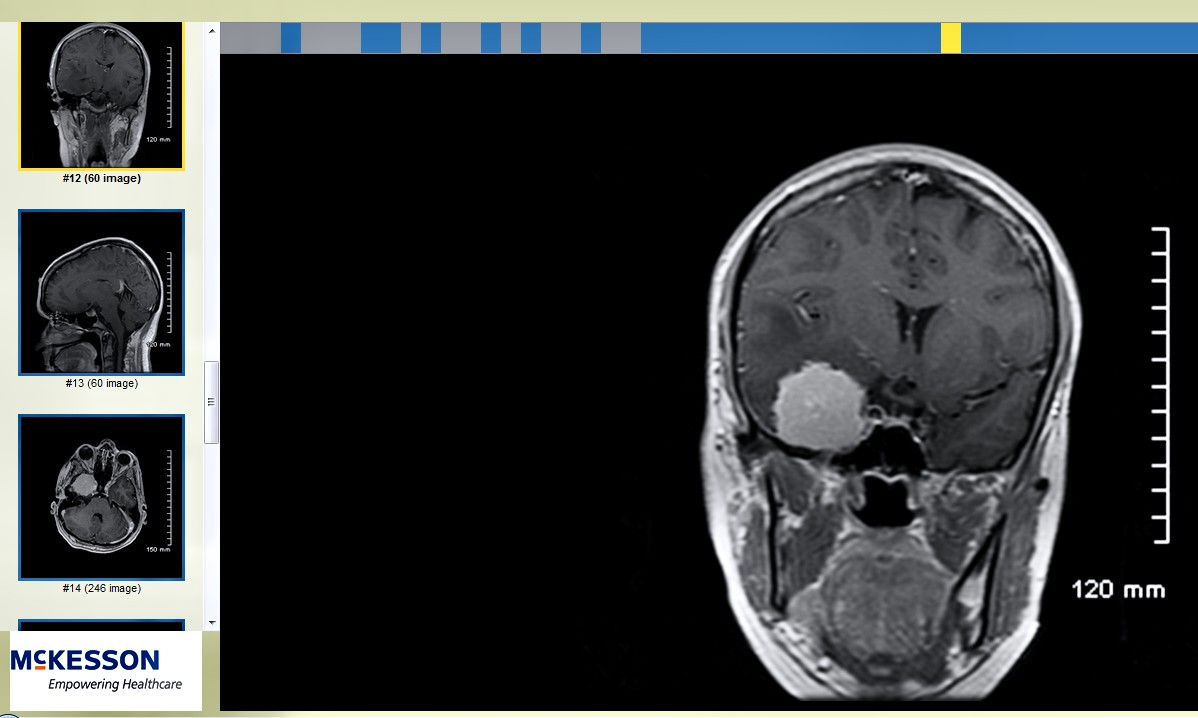

A black and white MRI of a golf-ball sized meningioma brain tumor on right with three small images of the same tumor along the left.

A CT scan reveals McClure’s golf-ball-sized tumor, which she lightheartedly named Fred — a foe she was determined to defeat. Photo/provided

McClure’s journey began in 2013 with a single nighttime seizure — and a shocking diagnosis: a meningioma tumor pressing behind her right eye. With no family history or known risk factors, the news was as unexpected as it was frightening.